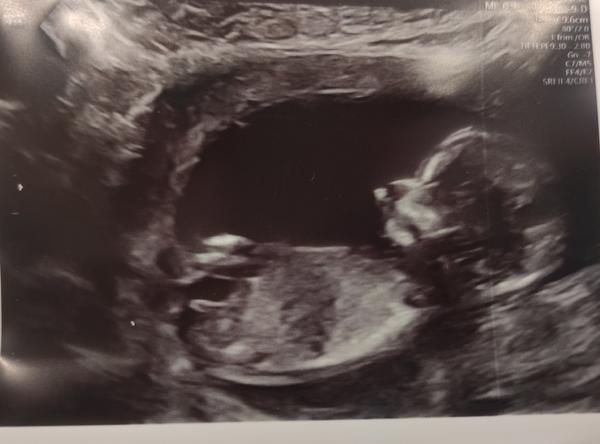

Ahoj holky, poznáte podle pohlavního hrbolku (pokud tam vůbec je 😂) pohlaví? Dnes na screeningu mi tvrdili, že je to chlapeček, ale já ať se koukám, jak se koukám, vychází mi to na holčičku 😂🤷🏻♀️

@chybadel joo? 😁 přijde ti ten sklon větší než 30°? 😁 mně to právě přijde souběžné 😁

Já bych podle této fotky tipla spíš holku… Všichni moji 4 kluci ten hrbolek měli výrazně nahoru oproti tomuto 🤷🏻♀️ To mě fakt zajímá, co poví příště 😁

Taky bych spíš řekla holka, ale přijde mně, že se trošku výš stáčí.., ale jestli se mně to nezdá, když vím, že to má byt chlapeček. Co máš doma?